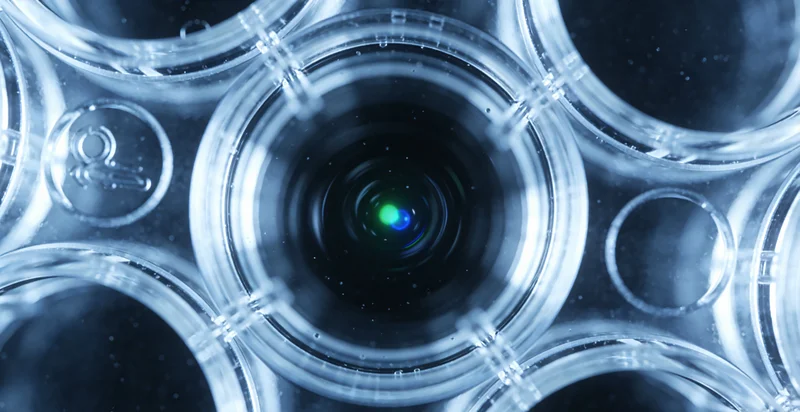

常规体检,如血常规、B超、胸片,是我们健康的基础防线,它们擅长发现已经形成的、结构或功能上比较明显的异常。但有些健康隐患,就像埋在地下的种子,常规检查可能探测不到。比如,极早期的微小肿瘤、尚未形成可见病灶的血管病变、神经系统的细微退变等。这时,全身MRI(磁共振成像)筛查的价值就凸显出来了。它是一种无辐射的精细“全身扫查”,能生成三维立体图像,对软组织、神经系统、关节、腹部脏器等显示得尤为清晰,能发现毫米级别的早期病变。

模块一:精密影像筛查(全身MRI)

- 影像检查:按照预约时间进行全身MRI扫描,需去除金属物品,平躺约40-60分钟,过程中保持安静即可。